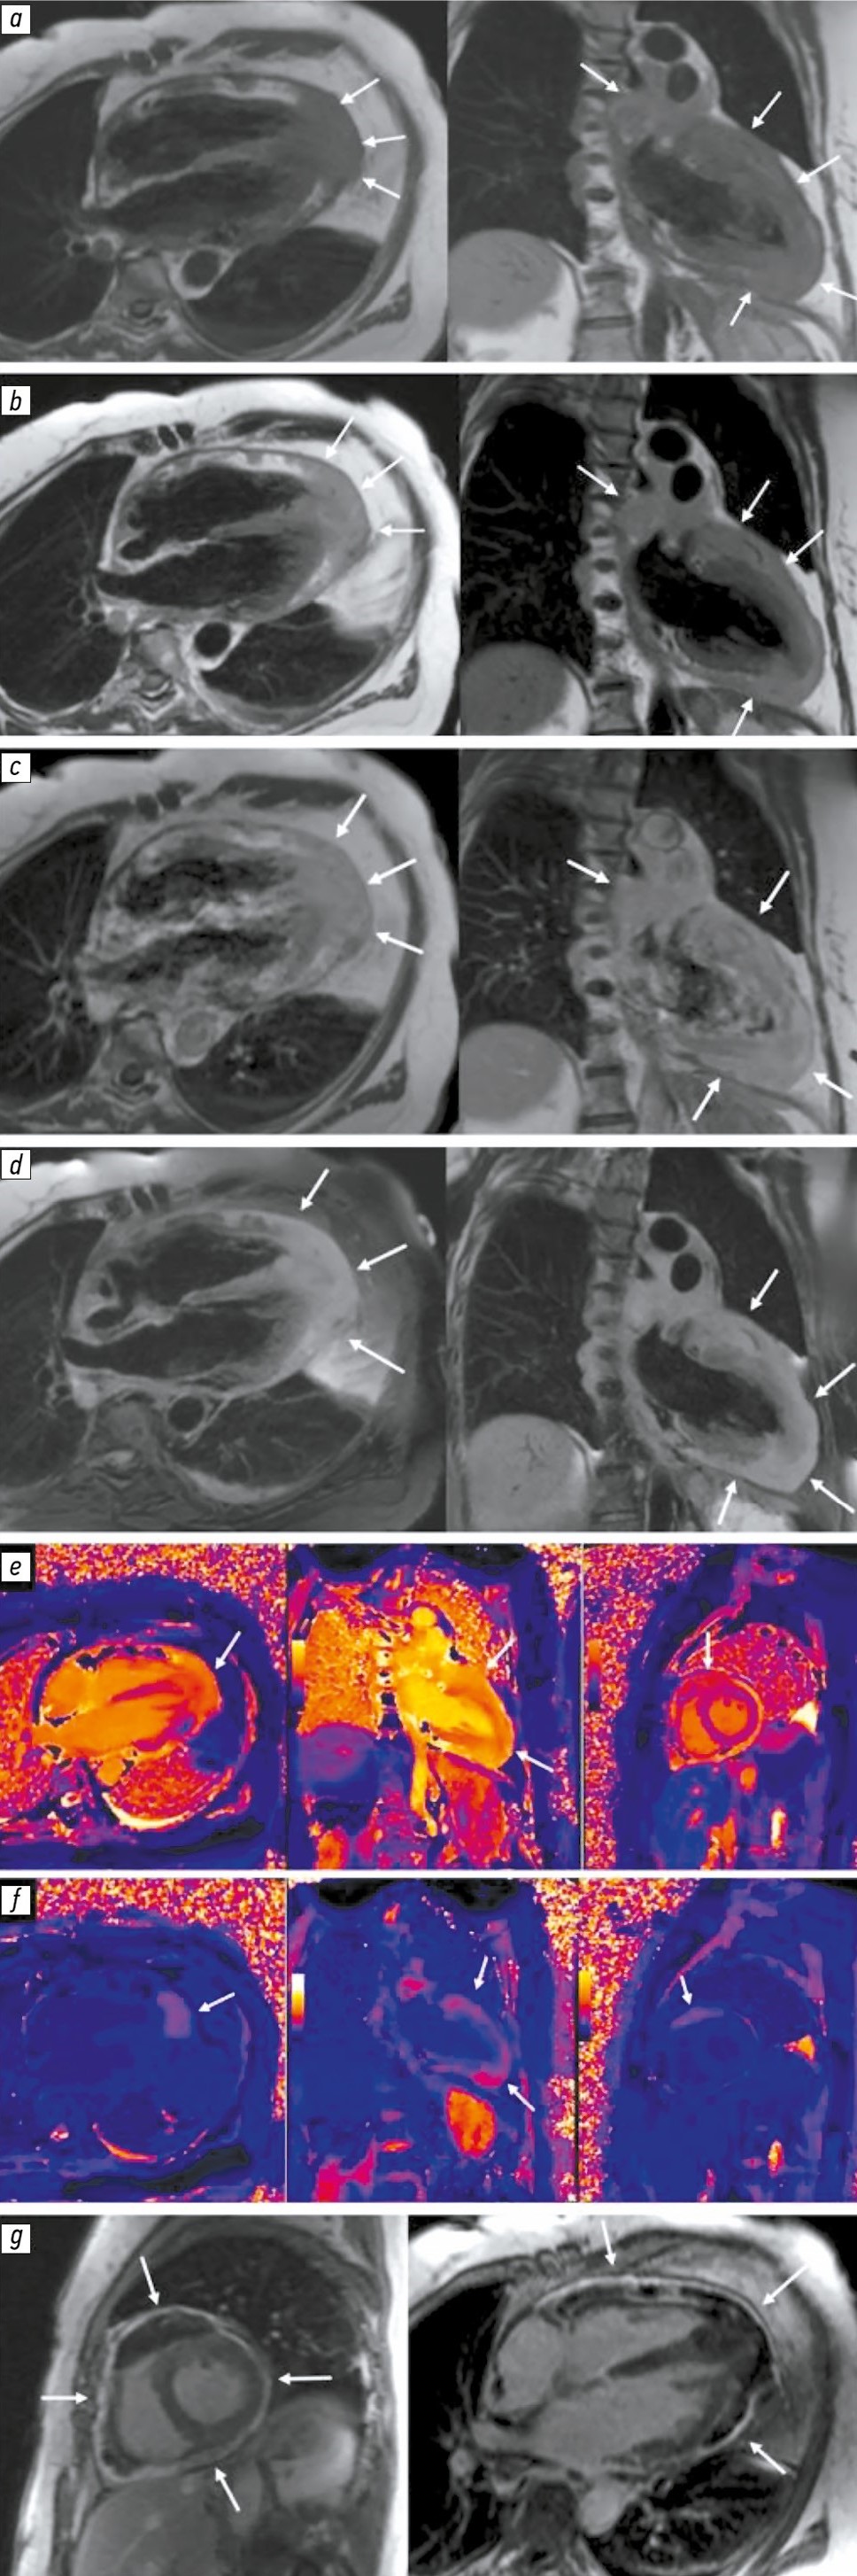

Mediastinal lymphoma with cardiac involvement mimicking acute coronary syndrome: a case report

Abstract

Lymphomas constitute a heterogeneous group of cancers characterized by uncontrolled clonal proliferation of lymphoid cells. They may arise in lymph nodes and extranodal organs and tissues. Primary mediastinal large B-cell lymphoma is a rare and aggressive subtype of B-cell lymphomas, accounting for approximately 2%–3% of all non-Hodgkin lymphomas.

This article presents a clinical case of primary mediastinal lymphoma with cardiac involvement in a 66-year-old female patient. The initial signs of the disease mimicked acute coronary syndrome, including chest pain, dyspnea, and cardiac rhythm disturbances. Diagnostic evaluation revealed a rapidly progressive mediastinal tumor invading the pericardium and myocardium, confirmed using modern imaging modalities (echocardiography, cardiac magnetic resonance imaging, and computed tomography) and pathological examination. Despite intensive treatment, the patient’s condition deteriorated rapidly, resulting in a fatal outcome.

This case highlights the diagnostic challenges associated with cardiac and pericardial involvement in mediastinal lymphomas and demonstrates the necessity of a multidisciplinary approach in the management of such rare and aggressive diseases.

647-658